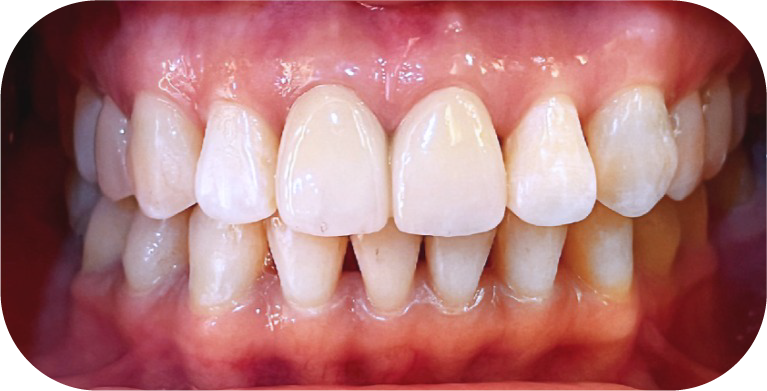

牙齒矯正